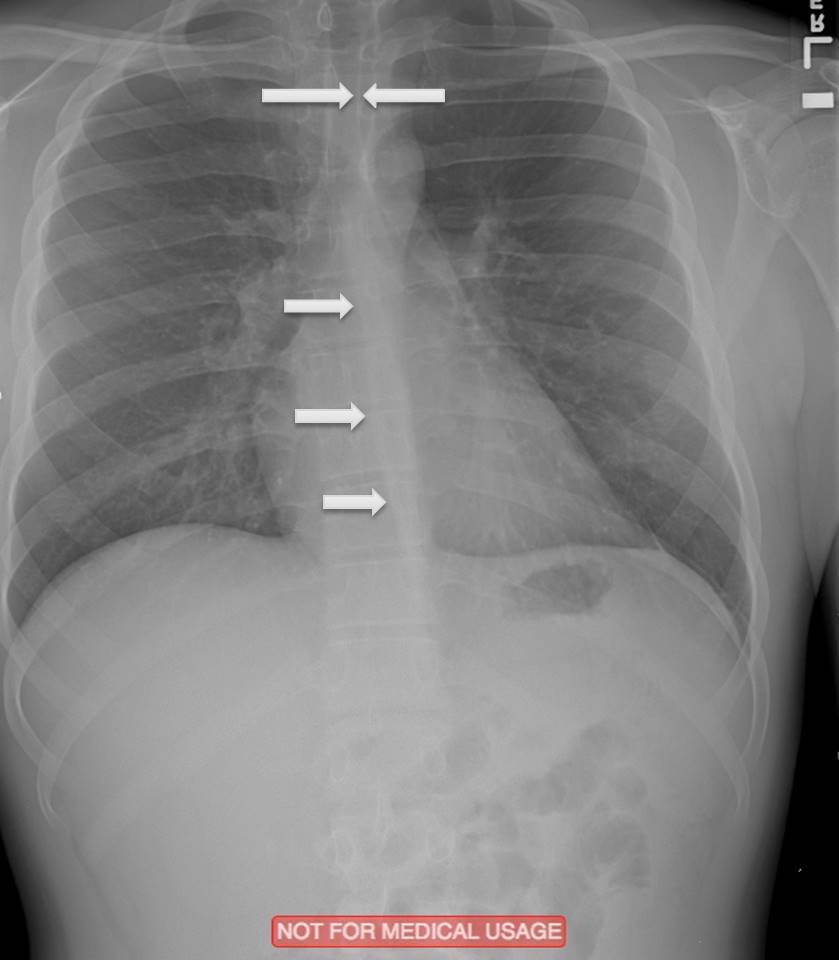

What do you see here?

Silhouette Sign, loss of defined heart border on left side